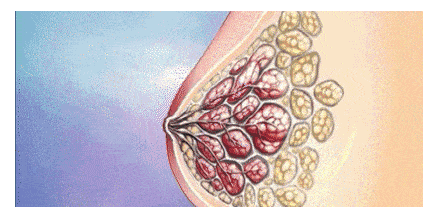

打个比方:松垂胸部的乳腺就像一瓣一瓣散开的橘子,散乱地堆积在乳房底部,靠皮肤兜着。现在,市面上很多医生只会做传统的下垂矫正手术,其只是将外部多余的皮肤切除,直接将乳房整体上提、缝合,没有对内部腺体组织做任何处理。

这种做法刚做完时胸部看着是提升了,但里面的腺体组织还是散乱地堆积在底部。随着时间的推移和重力的影响,剩下的皮肤会逐渐变松弛,进而再次出现胸下垂。

以上这种“治标不治本”的胸下垂矫正还有一个问题,就是没有对腺体组织进行塑形复位,胸部上极依旧空瘪,形态也会差强人意。